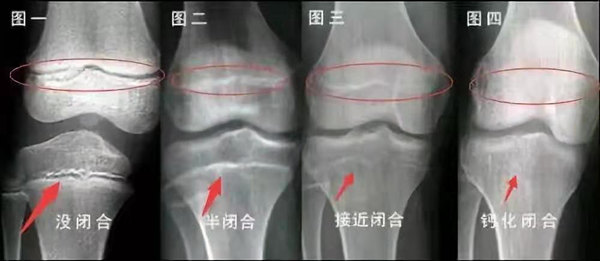

未成年時隨著年齡的增加骺軟骨端不斷骨化,骨骼就不斷增長。當骨骺線完全閉合時骨骼就停止生長,個子也就不再增長了。一般骨骺端完全閉合的年齡是18~20歲左右。

骨骺線提前閉合最多見的情況是性早熟,而這也是很多醫(yī)生專家建議孩子進行骨齡測量的原因之一。另外,在兒童時期大量補鈣也會使骨骺端提前過早閉合。

青少年一般什么時候骨骺閉合?

一般女孩是在16歲,男孩是在18歲。

一般來說,女孩的骨齡超過14歲,男孩的骨齡超過16歲,這時其骨骺線已接近閉合,基本沒有長高的機會了。

因此,越早了解骨骺線閉合情況,越早干預(yù),孩子長高的可能性越大。